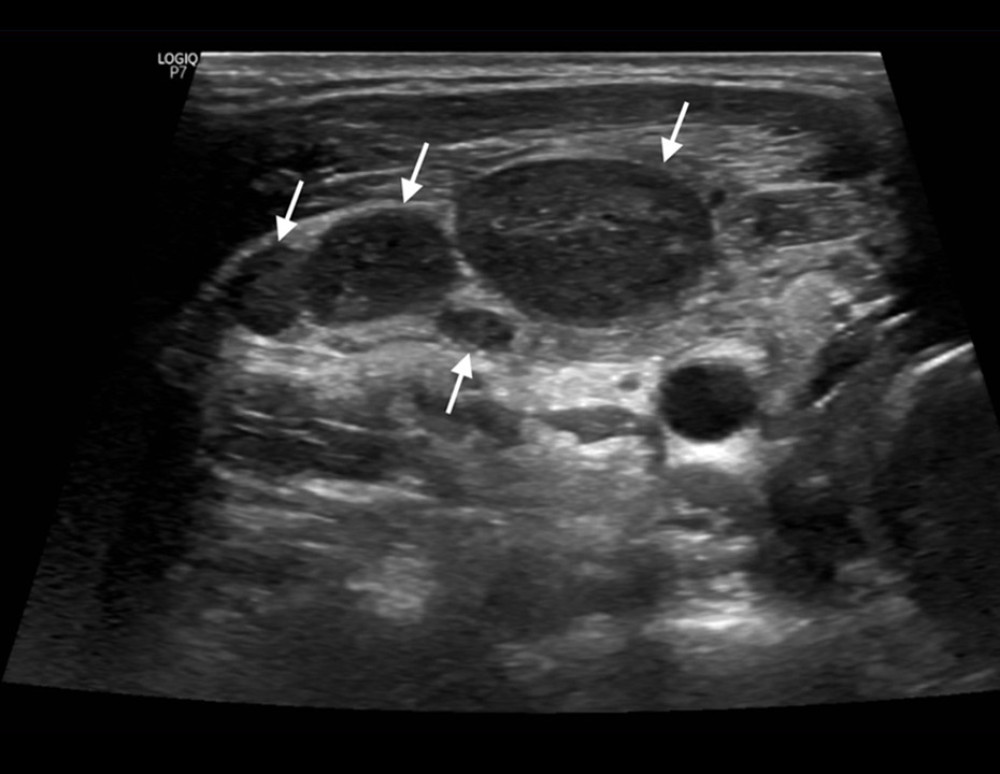

Kikuchi-Fujimoto Disease In The Regional Lymph Nodes With Node

Kikuchi-Fujimoto disease in the regional lymph nodes with node spandidos-publications.com